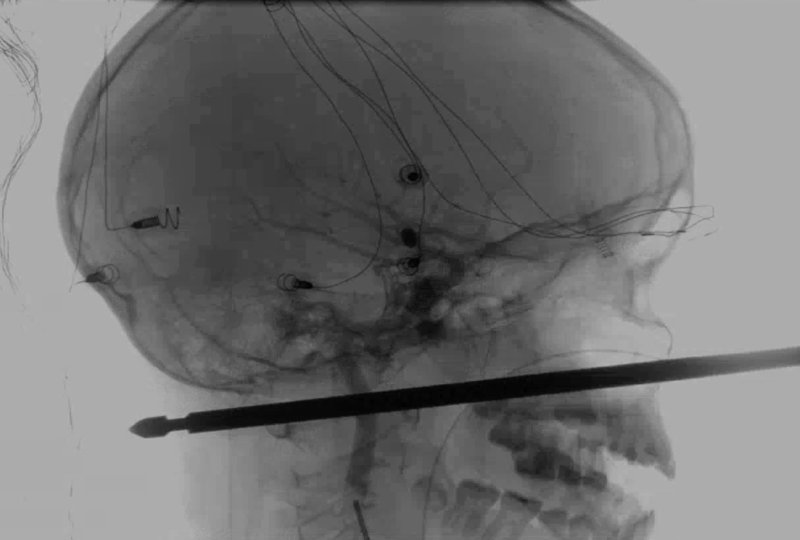

Niño sobrevive luego que brocheta le atravesó la cabeza (Video)

La brocheta le había atravesado la cabeza y unos 15 centímetros (medio pie) de la estaca le sobresalía por la cara.